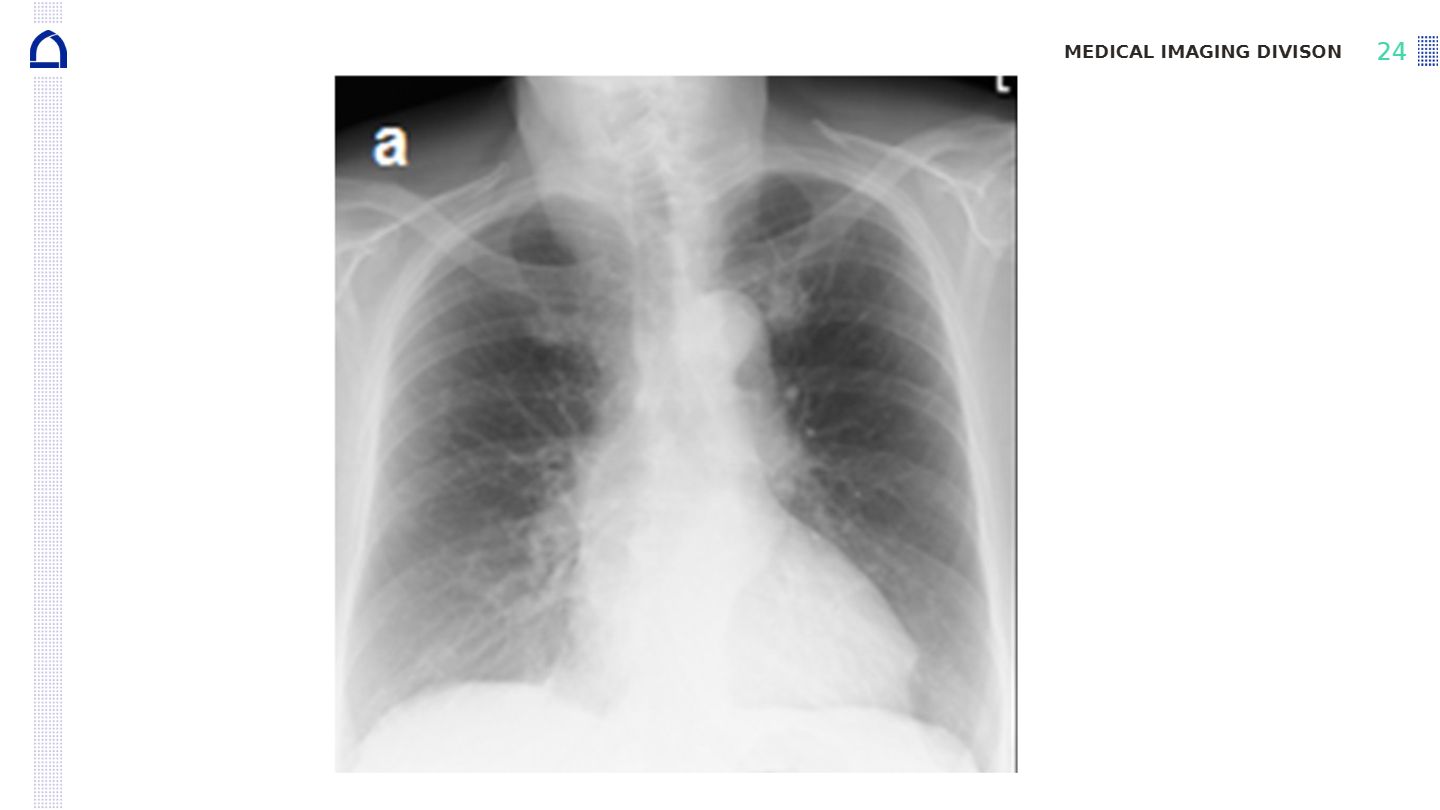

Compare the images shown after soft tissue removal and bone removal in dual energy subtraction. What differences can you observe and what clinical advantages do these differences provide?